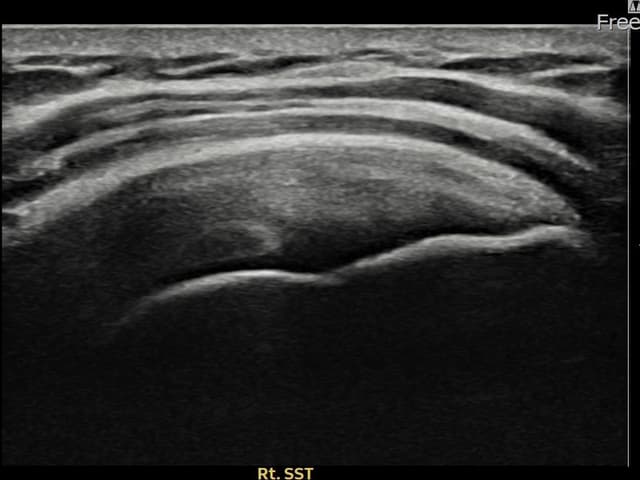

右侧 冈上肌腱 石灰化肌腱炎

14mm × 10mm

13mm × 9mm